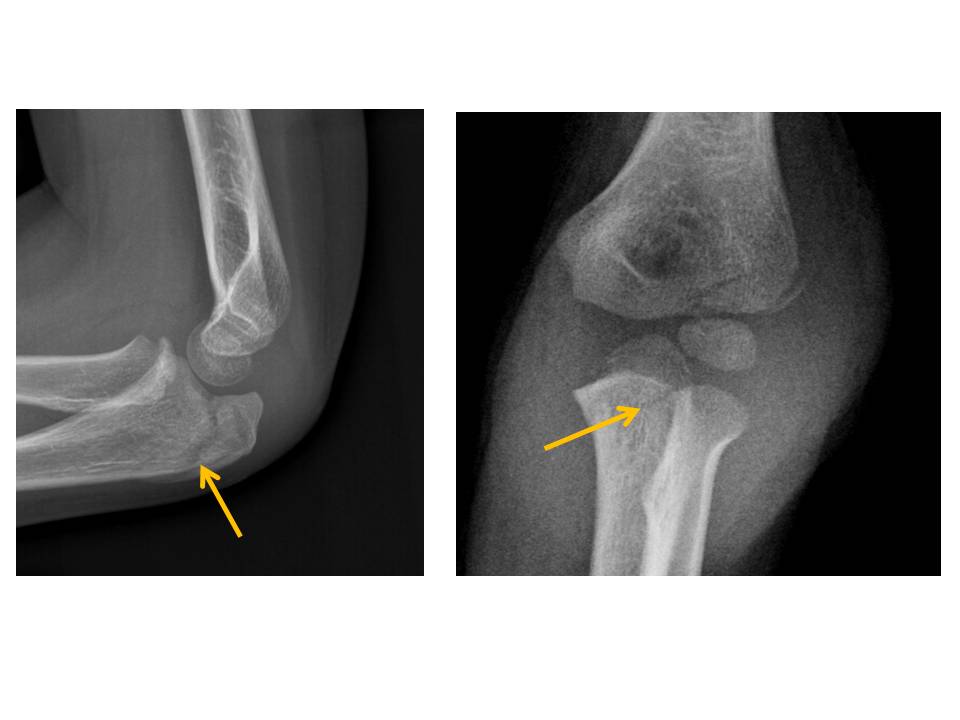

The proximal radius is fractured. [Yes/No]

The medial or lateral humeral condyles are fractured. [Yes/No]